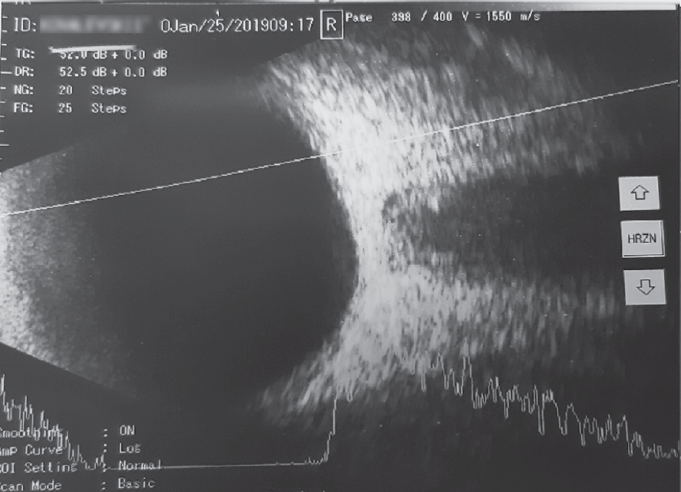

При сканировании в В-режиме после курса лечения препаратом «Витрокап» в 32 % случаев отмечено уменьшение количества помутнений, что соответствовало снижению количества эхопиков на А-сканировании (рис. 4, 6, 8), в большинстве случаев (80 %, р < 0,05) происходило снижение высоты эхопиков при А-сканировании в зоне их максимальной концентрации (см. рис. 4, 8).

Рис. 8. A- и B-сканирование пациента К. после курса препарата «Витрокап». В-скан: аксиальная горизонтальная проекция; незначительное количество помутнений в стекловидном теле. А-скан: 4 эхопика низкой эхогенности

Fig. 8. After a course of the drug “Vitrocap”, patient K.: B-scan: axial horizontal projection, a small amount of “clouding” in the vitreous body. A-scan: 4 peaks of low echogenicity